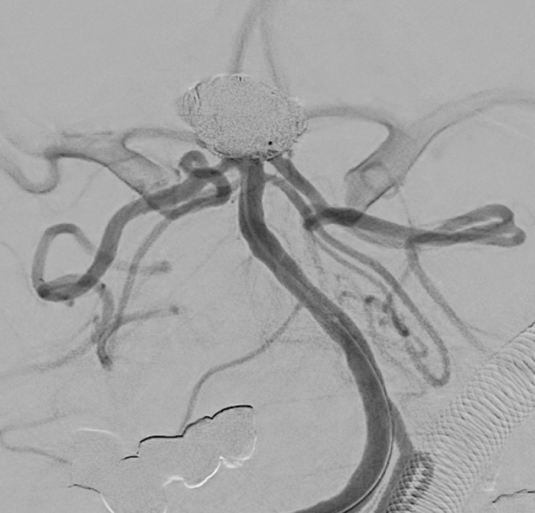

Apoplexy 9

【A】

Apoplexy 10

【B】

Apoplexy 11

【C】

Apoplexy 12

【D】

血管内治療にて血栓除去術施行。A;右中大脳動脈が閉塞している。B:ステントレトリーバーを閉塞部位で展開。C;再開通後。D;除去した血栓。